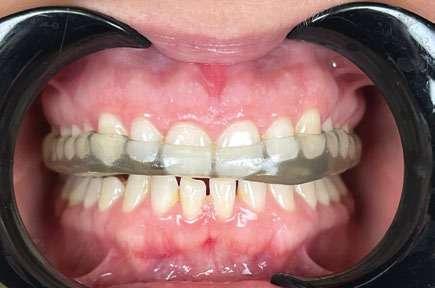

2. Análisis intraoral (Ilustración 2 y 3):

 Clase III molar y canina de Angle bilateral.

 Mordida abierta anterior > 3 mm.

 Compresión maxilar junto con mordida cruzada posterior bilateral.

 Línea media inferior desviada 2 mm hacia la derecha.

Ilustración 2. Fotografías intraorales iniciales de estudio.